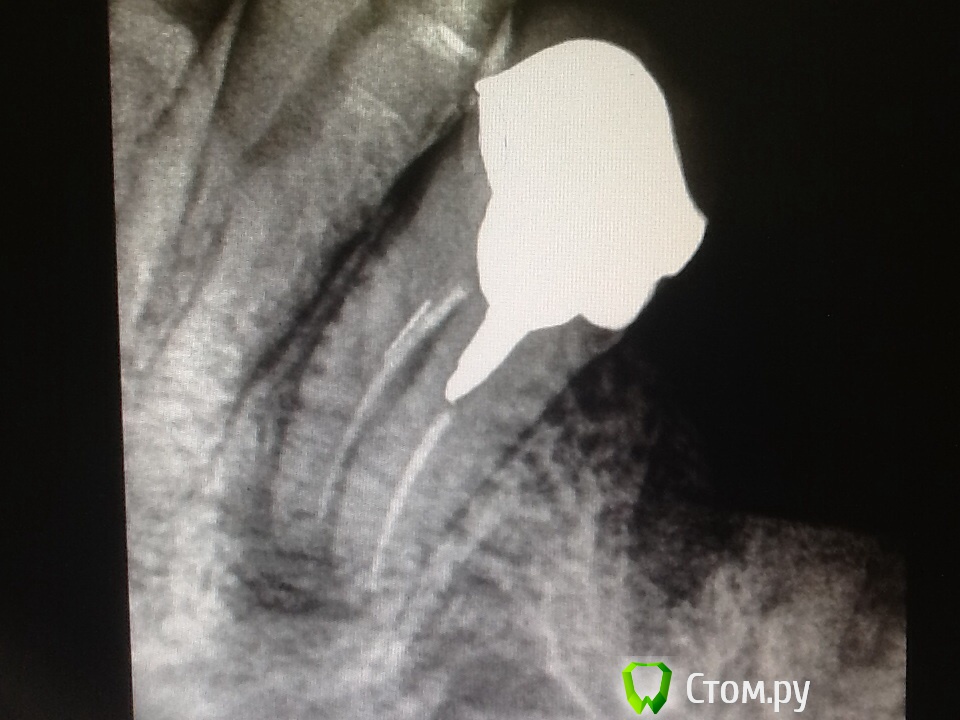

Л Ю С Я Опубликовано 19 ноября, 2014 Поделиться Опубликовано 19 ноября, 2014 Реколл через 5 месяцев. Жалоб нет. Вроде все неплохо, но не нравится латеральная поверхность ближе к 3.4 . Отправила на кт ( через 2 месяца) 2 Ссылка на комментарий

faity Опубликовано 19 ноября, 2014 Поделиться Опубликовано 19 ноября, 2014 Дистально кость уходит или контраста не хватает? Ссылка на комментарий

Л Ю С Я Опубликовано 19 ноября, 2014 Поделиться Опубликовано 19 ноября, 2014 Дистально кость уходит или контраста не хватает?Выводила чтоб больше видна была мед поверхность, поэтому и выглядит так с дистальной Ссылка на комментарий